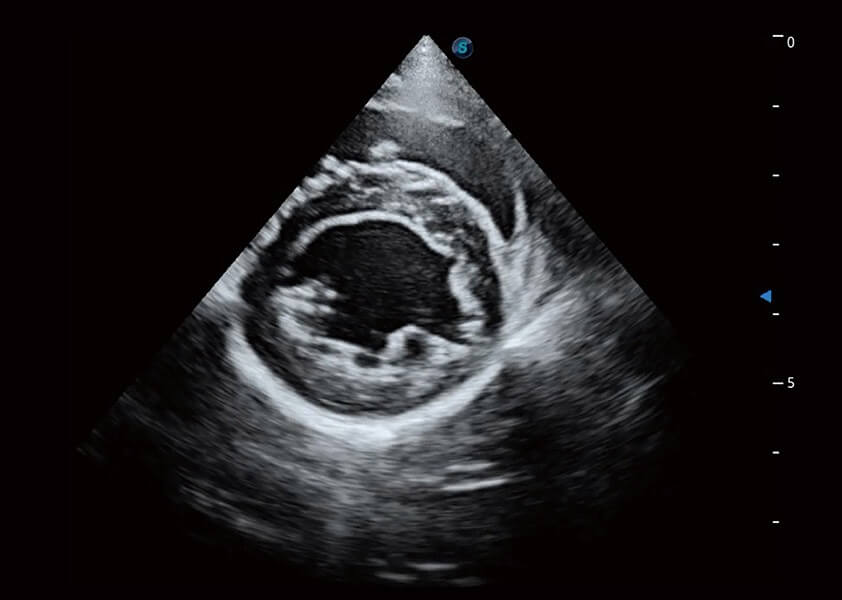

优异的基础图像

(犬)乳头肌短轴